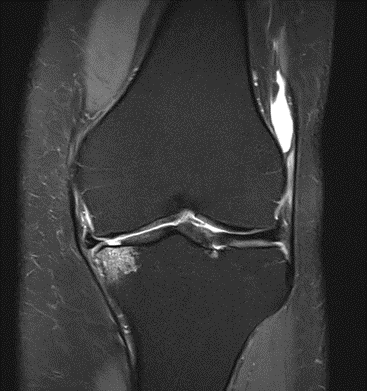

MRI scans illustrating the improvements regarding Group 2 are presented below, showing pre-treatment images with evident cartilage defects, pronounced bone marrow edema, and synovial inflammation, followed by post-treatment scans demonstrating improved joint structure, reduced edema, and decreased inflammation (Figures 12-29).

MRIs of Group 1

To provide a comparative perspective, additional MRI scans from Group 1 are shown subsequently. While patients in this group also displayed reductions in bone marrow edema, effusion, and synovitis, the improvements appeared less pronounced than those seen with the combined therapy. Pre-treatment MRI scans revealed extensive edema and synovial inflammation, which were partially reduced at the 2-month follow-up. However, residual joint effusion and subtle signs of inflammation remained present in some cases. These findings further support the potential benefit of combining the ChondroFiller® liquid with MSC therapy to achieve more comprehensive structural improvements and facilitate enhanced cartilage regeneration (Figures 30-41).

Figure 30: Female, 72 years, pre-intervention MRI.

Figure 31: Female of figure 30, two-month follow-up MRI: MSC only.